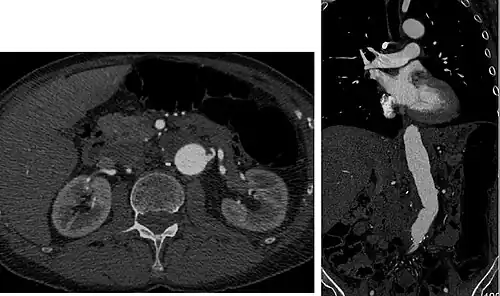

Aorta and great arteries

CTA can be used in the chest and abdomen to identify aneurysms in the aorta or other major blood vessels. These areas of weakened blood vessel walls that bulge out can life-threatening if they rupture. CTA is the test of choice when assessing aneurysm before and after endovascular stenting due to the ability to detect calcium within the wall.[3] Another positive of CTA in abdominal aortic aneurysm assessment is that it allows for better estimation of blood vessel dilation and can better detect blood clots compared to standard angiography.[4]